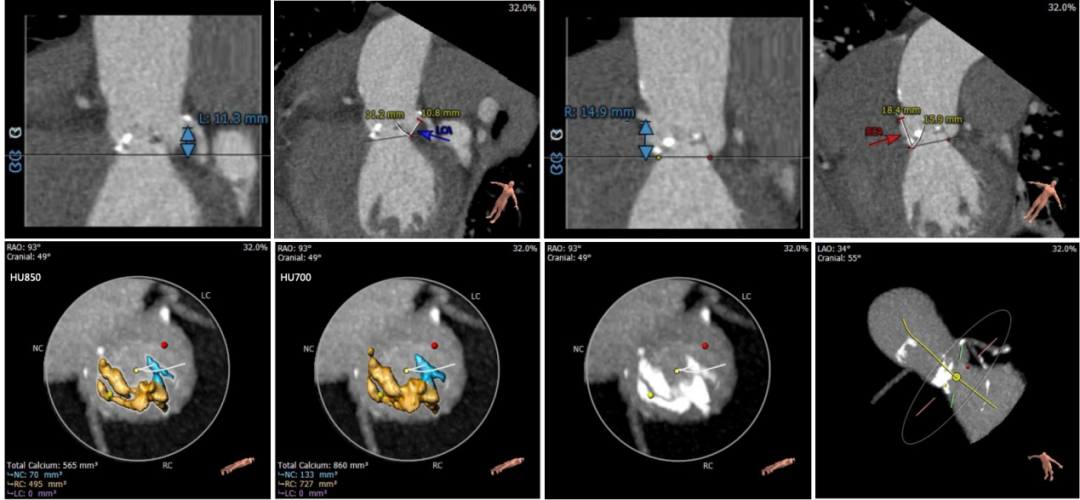

术前CT评估

Type0型二叶式主动脉瓣,重度钙化,钙化发布不均,位置靠右前侧,根据钙化形态预估,术中钙化推移难度较大,对人工瓣膜形态影响较大,存在人工瓣膜移位及瓣周漏风险。

左冠高度稍低,左冠起始处可见局限钙化,左冠瓣瓣叶长度偏长,综合瓦氏窦内径等因素考虑,左冠存在遮挡风险。

入路血管多处钙化,腹主动脉分叉前病变较重,双侧血管内径良好,整体入路血管条件尚可。

主动脉根部测量

瓣上结构测量

冠脉阻挡风险及钙化评估

外周血管入路评估